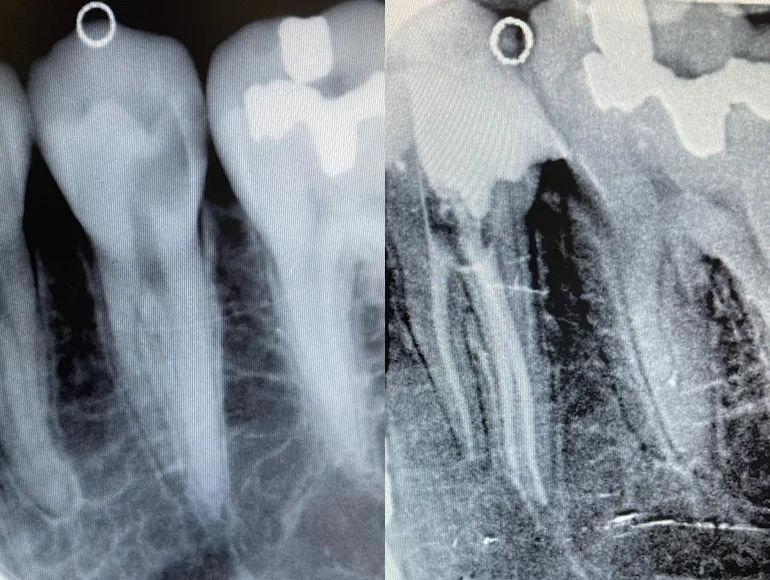

Retreatment of Rootcanal

Case by Dr. Taha Azimaie: Retreatment of failed rootcanal can give a patient another chance to retain the tooth. Retreatment is case selective and not all failed rootcanals are treatable. In this case root canal has failed due to poor sealing of the canals (The white lines in the roots) during the first treatment. Please note the sharp deviation of the canal at the tip of the root (the white line)